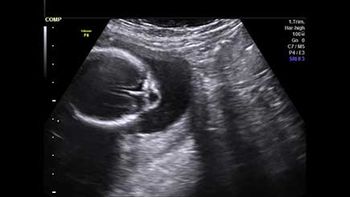

Challenge your diagnostic skills: Anything unusual about this fetal head?